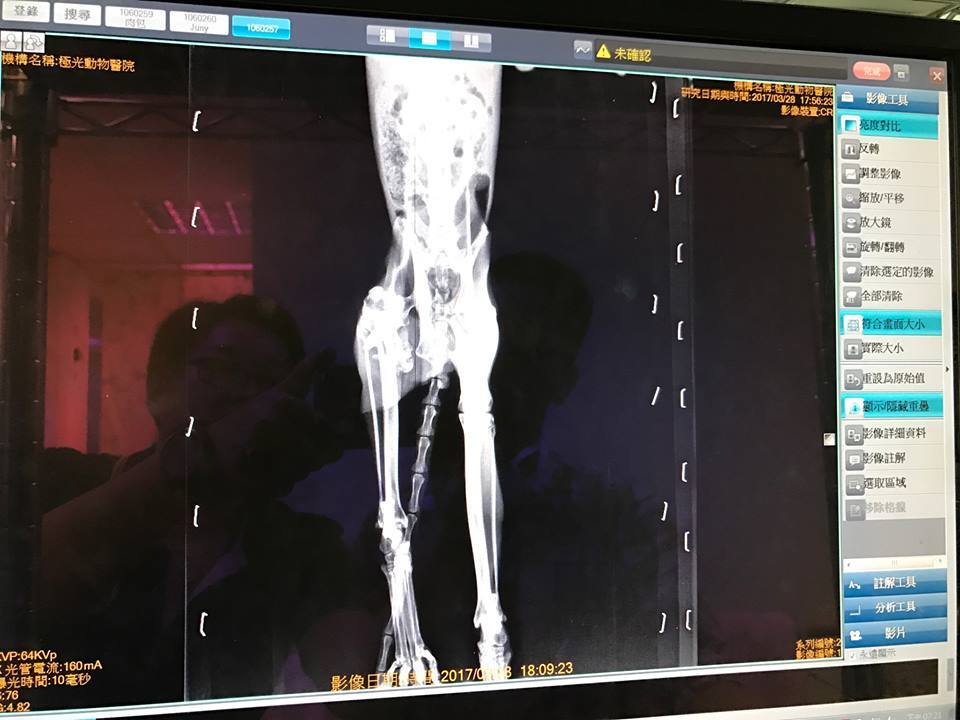

3/28~4/1住院期間

醫生為乖耶進行了血檢

以及愛滋、白血和小病毒的快篩

以及X光下看檢視乖耶的骨頭狀況

並且由於乖耶糞檢中有不少的蛔蟲

不停腹瀉及軟便

除了給予驅蟲藥外,也同時給予止瀉藥

出院後乖耶必須關籠觀察行走狀況

若是可以走路,不動手術也沒關係

若是無法走路,

則到時須選擇替乖耶截肢,

或是動大手術把沾黏的肌肉剝開再處理黏住的斷骨…